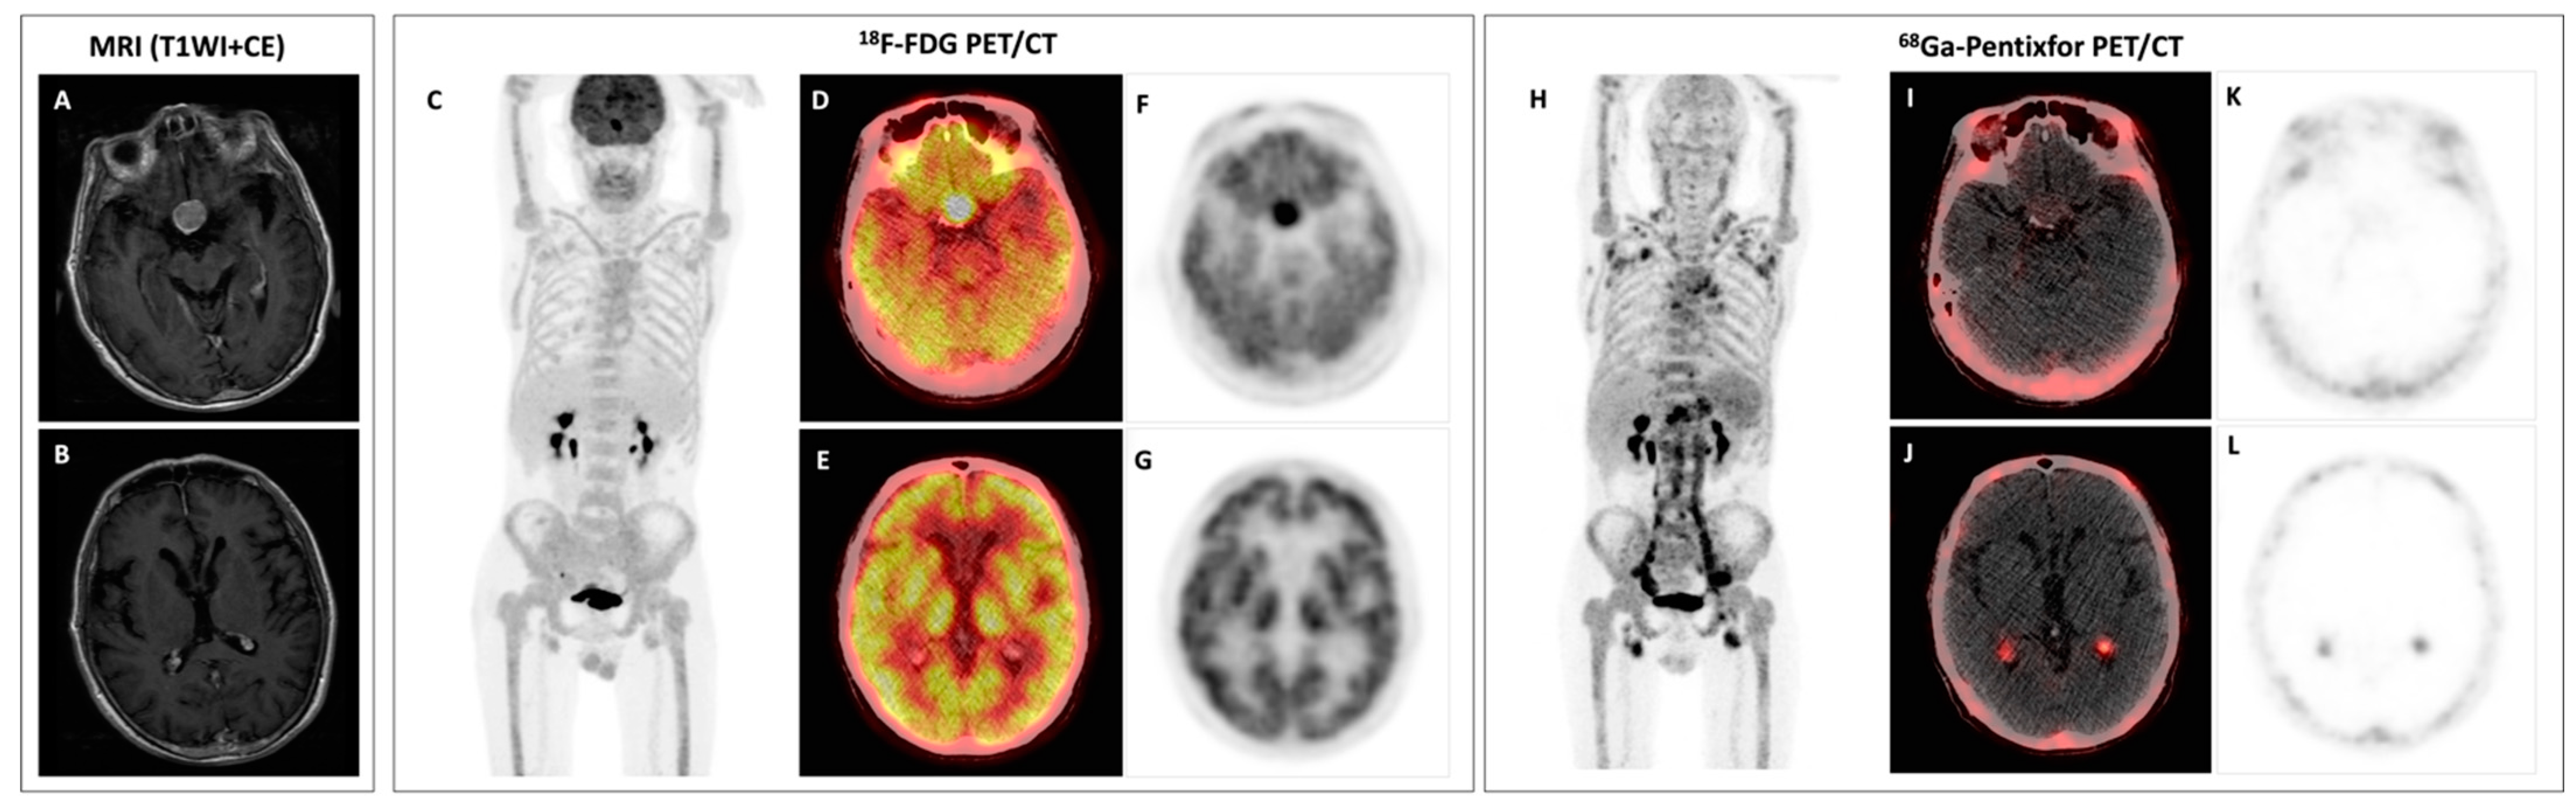

Bing–Neel Syndrome and Coexisting Pituitary Macroadenoma in a Patient with Waldenström Macroglobulinemia Revealed by 18F-FDG and 68Ga-Pentixafor PET/CT

Pan, Q.; Luo, Y.; Cao, X.; Li, J.; Feng, J. Bing–Neel Syndrome and Coexisting Pituitary Macroadenoma in a Patient with Waldenström Macroglobulinemia Revealed by 18F-FDG and 68Ga-Pentixafor PET/CT. Diagnostics 2023, 13, 1334. https://doi.org/10.3390/diagnostics13071334